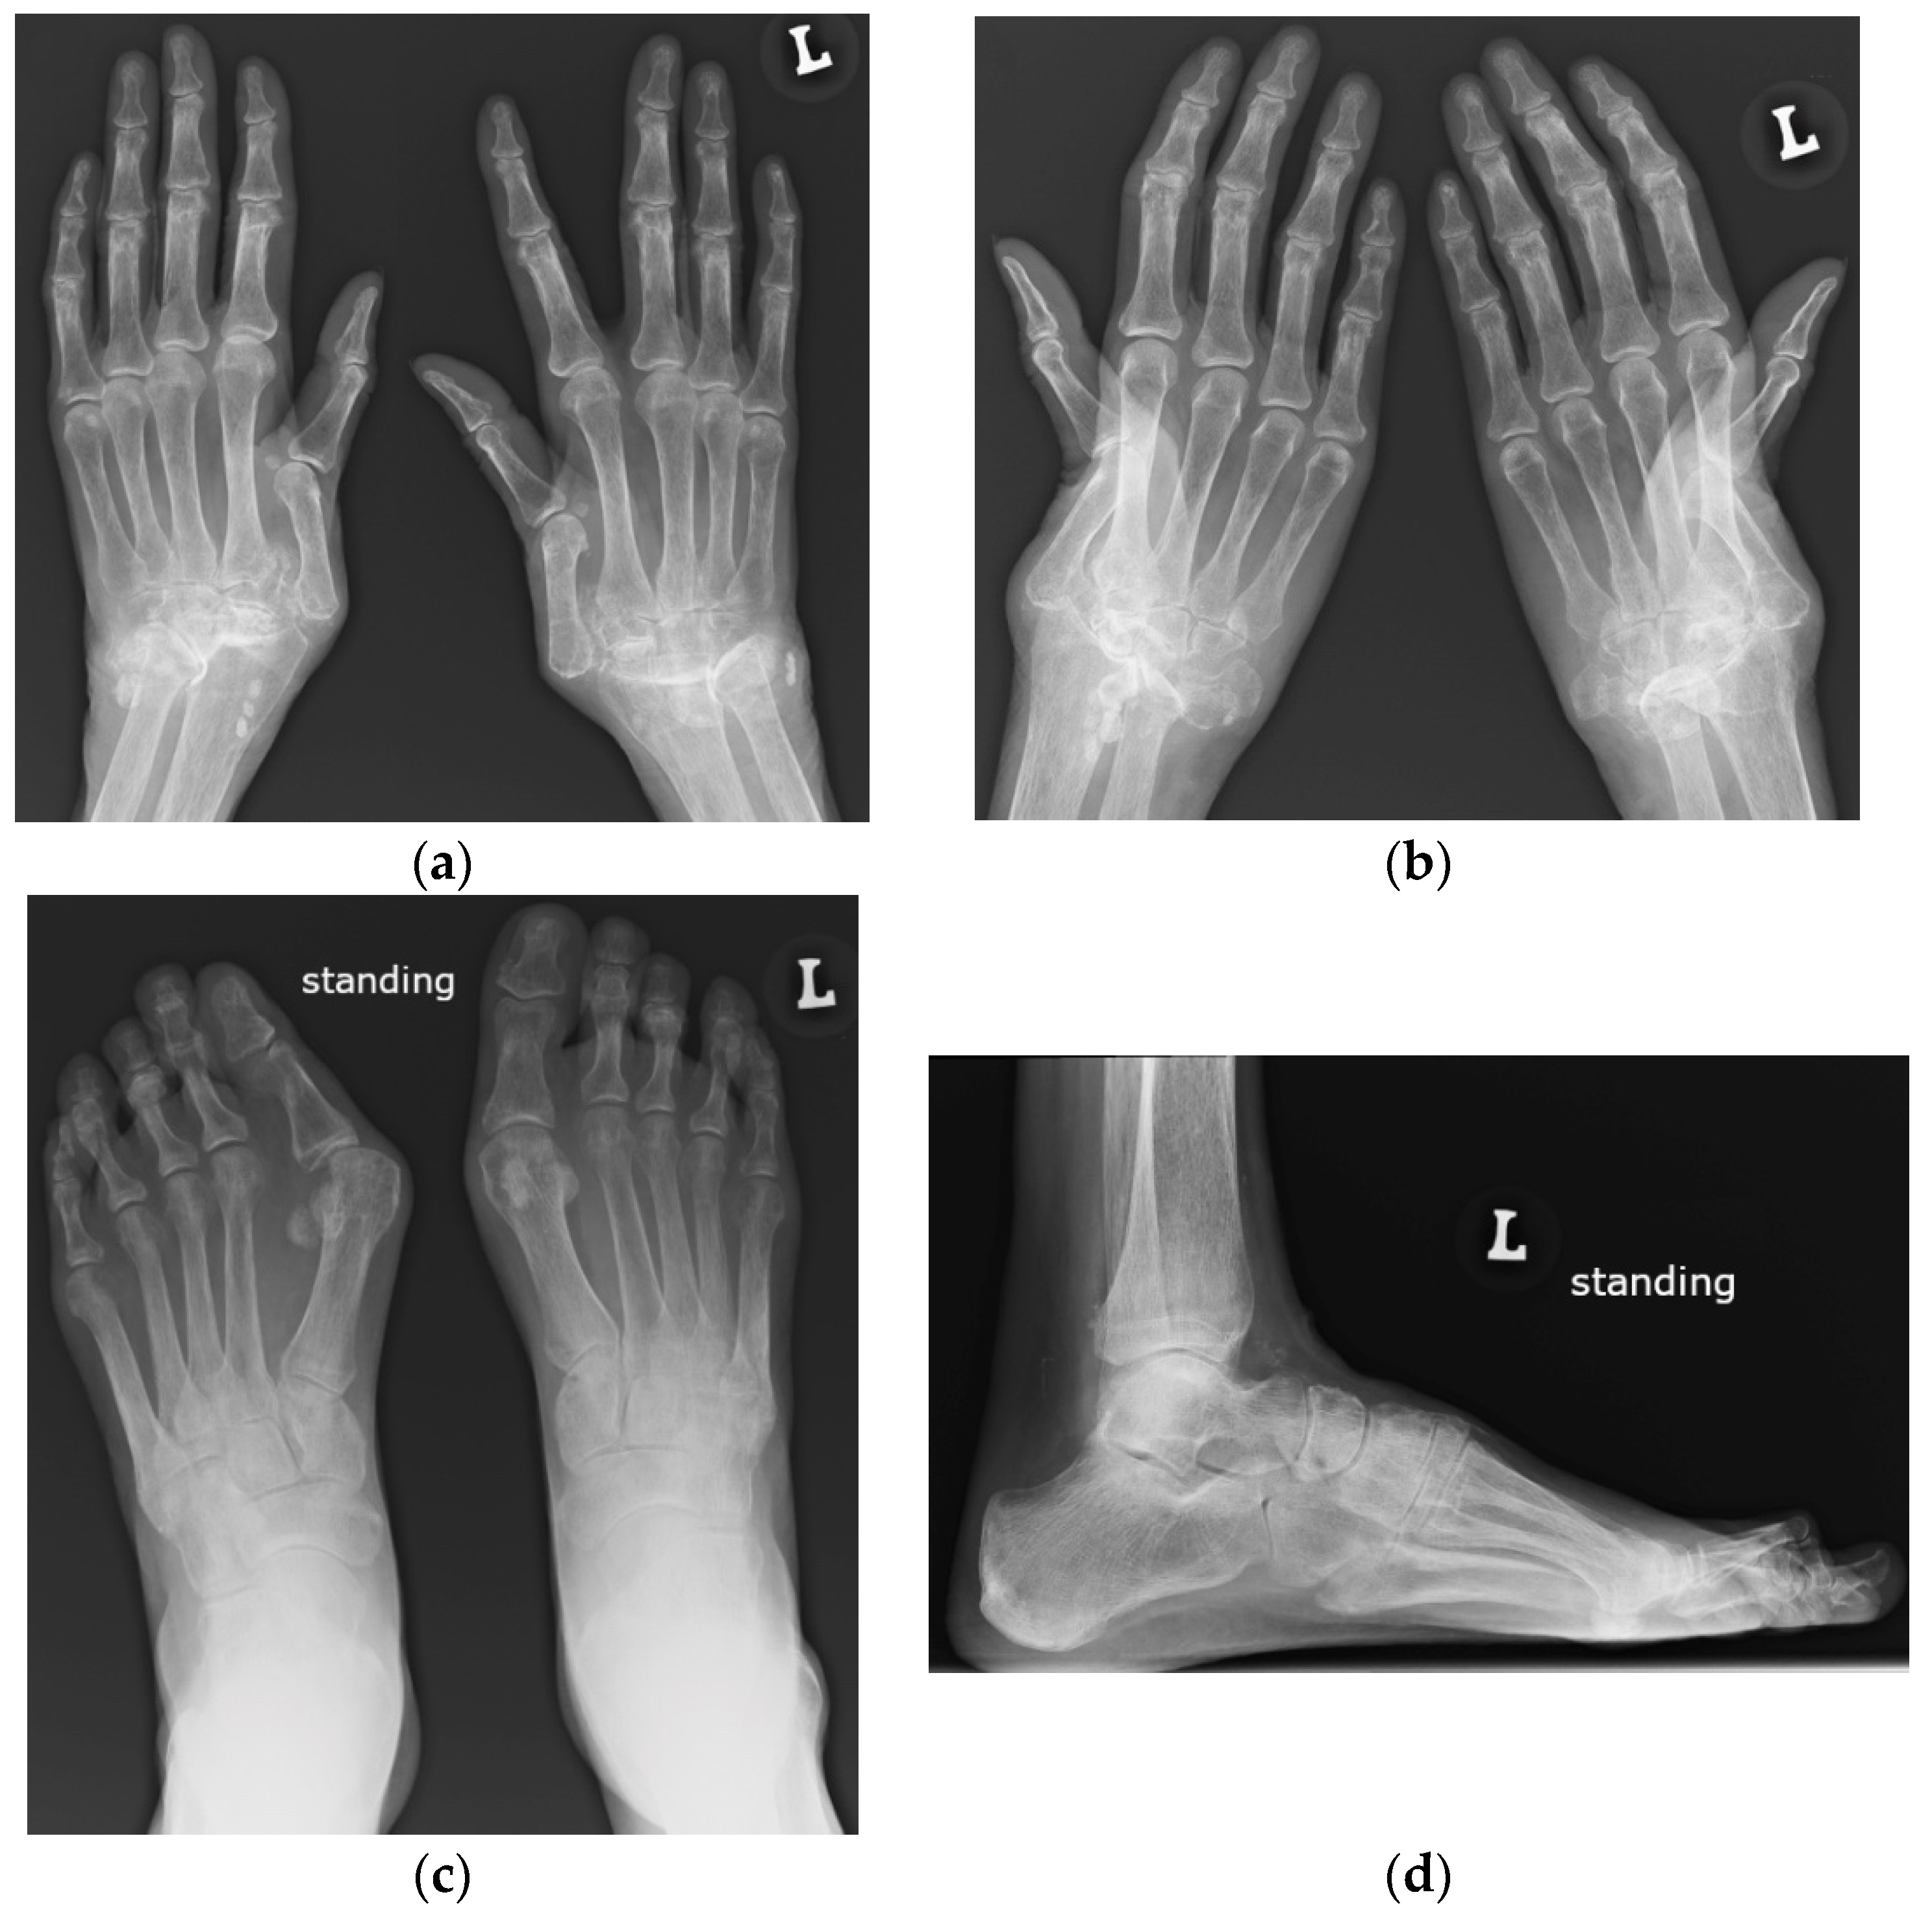

Figure 2.

A 63-year-old male with systemic lupus erythematosus and Jaccoud’s deformities on clinical examination. (a) Posterior–anterior and (b) oblique radiographs of the bilateral hands show ulnar deviation of the lesser finger phalanges of the right hand, with malalignment of the 3rd–5th digits proximal interphalangeal (PIP) joints that are more apparent in (b). They also show contracture at the 3rd PIP joint of the left hand, osteoarthritis of the bilateral wrists and scattering of the metacarpophalangeal (MCP) joints, bilateral positive ulnar variance, and posttraumatic deformities of the bilateral distal radial metaphysis and of the distal right 5th metacarpal. (c) Axial postcontrast T1-weighted magnetic resonance image with fat saturation of the right hand shows MCP joints 2, 4, and 5 synovitis (short arrow pointing to MCP 4), MCP 2, 4, and 5 capsular enhancement (long arrow pointing to MCP 5), and 2–5 flexor tendons tenosynovitis (arrowhead pointing to middle finger flexor tendon sheath).

Figure 4.

A 64-year-old female with SLE diagnosed in 1980 with Jaccoud’s arthropathy for hands and feet. (a) Posterior–anterior and (b) oblique radiographs of the hands show bone demineralization; soft tissue swelling at the wrists; periarticular calcifications; malalignment at the distal radioulnar, radiocarpal, and midcarpal joints; dislocation of the 1st carpometacarpal and subluxation of the 1st metacarpophalangeal joints; and joint space narrowing with cyst-like and erosive/destructive changes consistent with rhupus syndrome. Note the reversible contractures at the proximal interphalangeal joints, apparent in (b) and resolved or less apparent in (a). (c) Anterior–posterior standing radiograph of the bilateral feet and (d) lateral standing radiograph of the left foot show bone demineralization, bilateral hallux valgus deformities, and bilateral 2nd and 3rd hammer toes, as well as a right foot with moderate lateral subluxation.